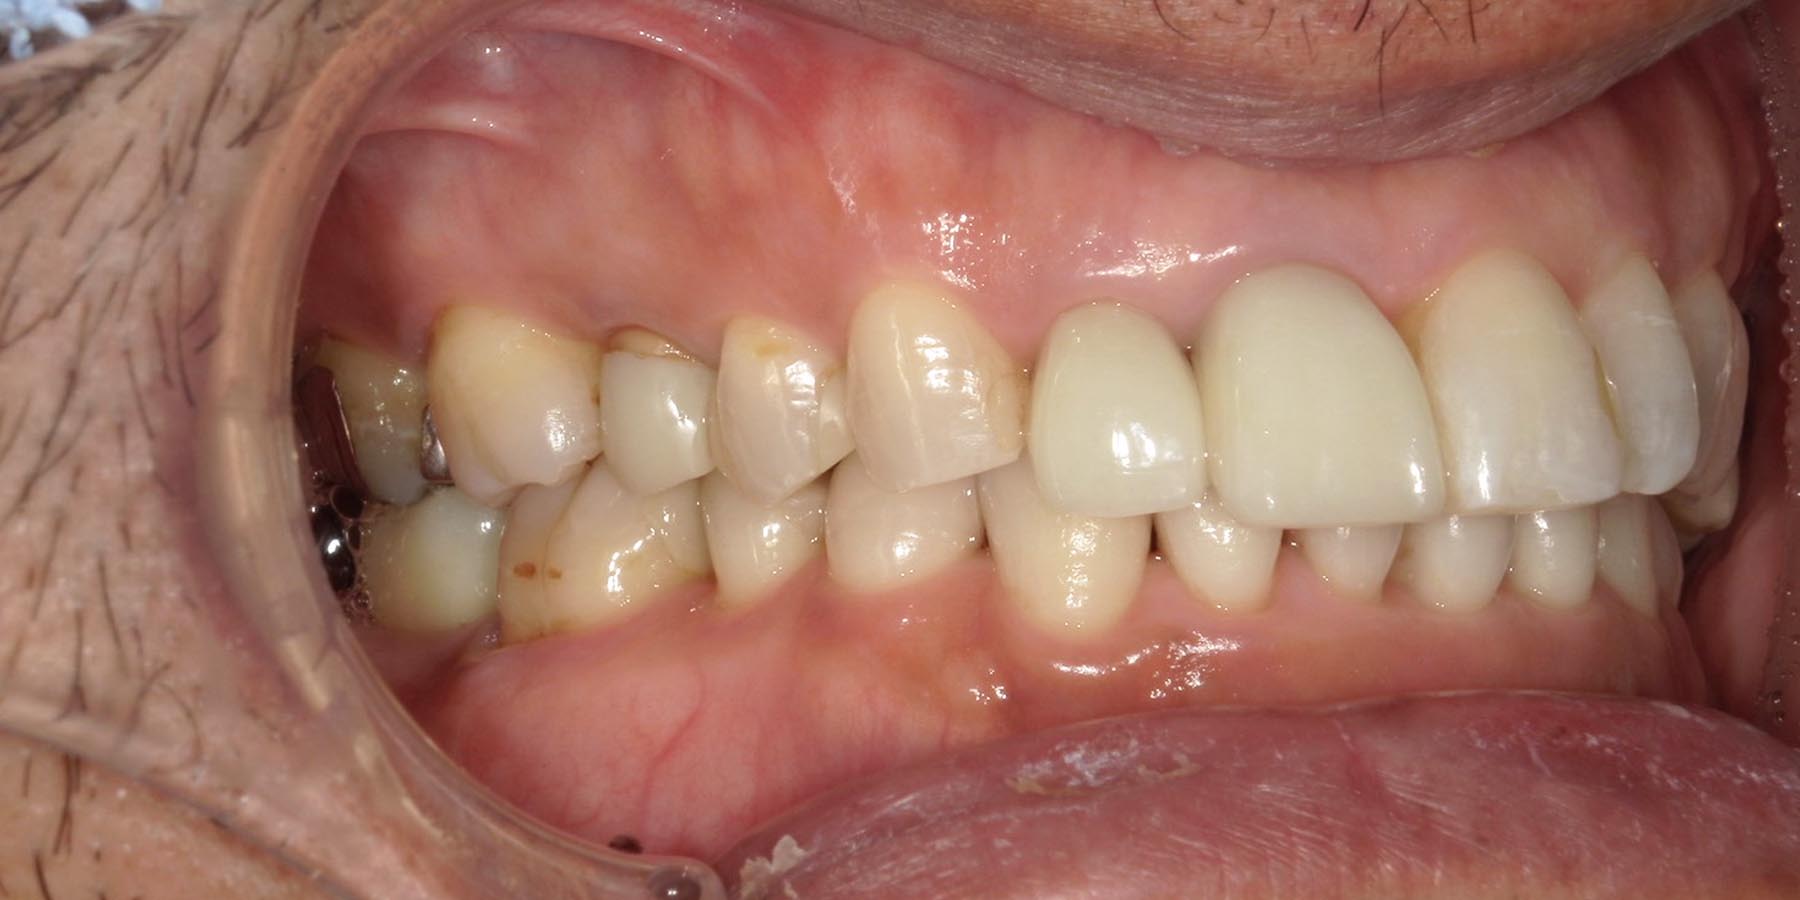

治療後

| 治療内容 | 矯正治療(前歯部) 右下7.左下5.6インプラント治療(3本) 前歯、奥歯セラミック治療(5本) |